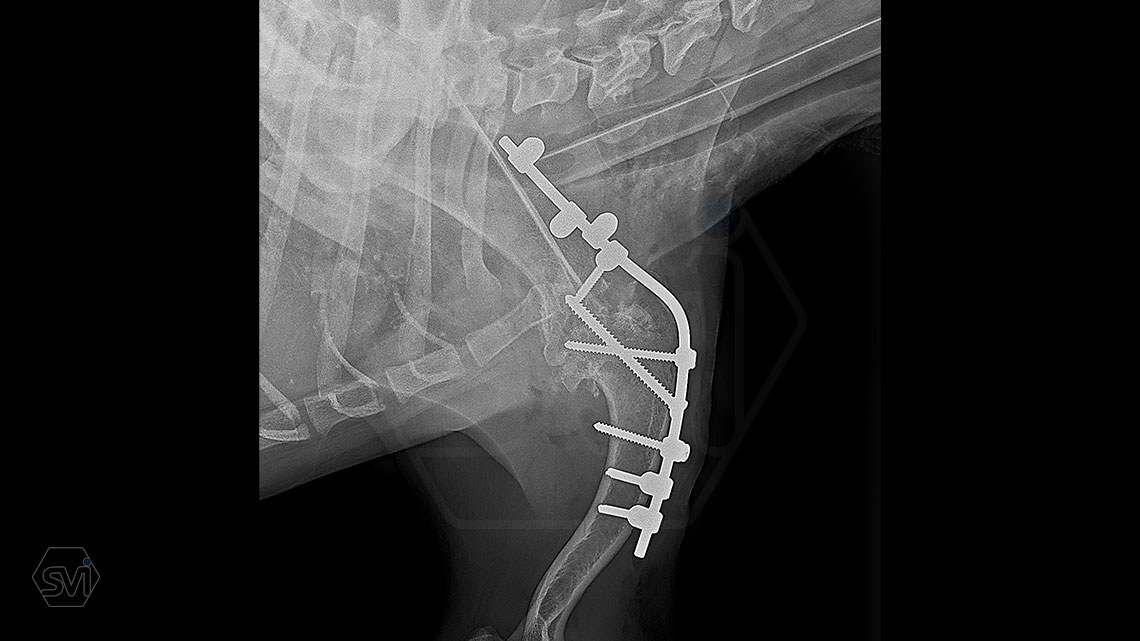

In our case, we created a shoulder arthrodesis on an 11-year-old 16kg female beagle dog with a 2.7 SOP-LC system and 4-4 clamps. The dog developed chronic arthritis and arthrosis, the biopsy did not confirm a tumor, only chronic inflammation.

There is no weak point in bridging the joint, which is inevitable in a plate bridging. Another great advantage is that the clamps can be placed according to anatomical needs, on either side of the rod and the screws can be inserted in any direction. Maximum stability is provided by the locking clamps, which is especially advantageous in a thin bone (scapula) or a bone with a porotic or thinned cortex (leg that has been used less for a long time). We have used the system several times in reoperations due to a broken plate.